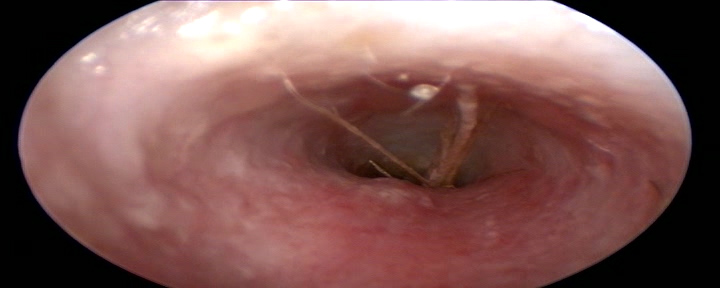

Zeker als uw hond door het gras wandelt en ineens een piep geeft en last lijkt te hebben van 1 oor is het van belang om niks in het oor te doen maar om op korte termijn het oor te laten controleren door uw dierenarts. Wanneer u het een paar dagen laat zitten is de kans groot dat de aar door het trommelvlies gegaan is en dan is hij vaak nauwelijks meer te pakken te krijgen.